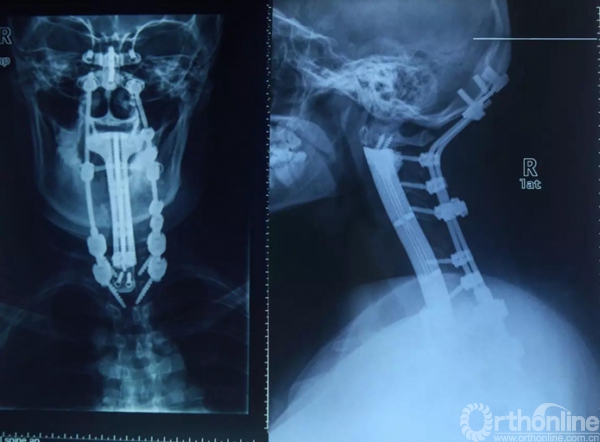

全颈椎椎体置换术后

据介绍,与以往的人工椎体相比,此次设计的3D打印全颈椎人工椎体,具有的海绵状微孔结构,有利于假体与邻近骨面的融合;同时假体中央留有植骨孔道,便于同种异体骨植入,最终实现生物融合。此外,假体头端外形也使重建更为稳固。